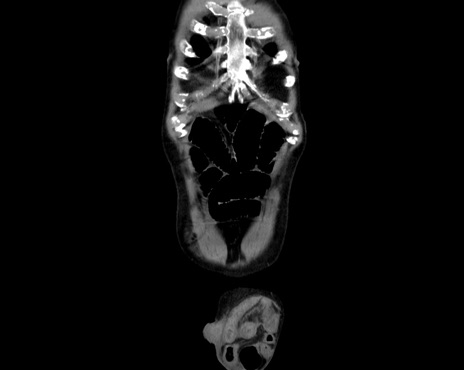

横断像